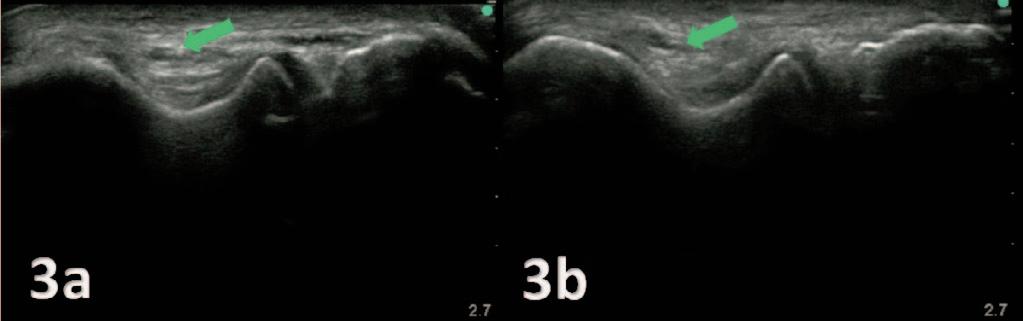

MSK ULTRASOUND BITES: TIPS AND TRICKS

Utilizing Diagnostic Musculoskeletal Ultrasound in the Evaluation of Cubital Tunnel Syndrome and Ulnar Nerve Pathology.

Manske RC, Voight M, Page P, Wolfe C.